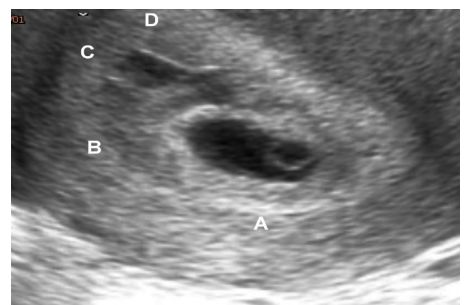

93 於民國 109 年 5 月 17 日,一位 27 歲許姓孕婦 G1P0 到院就診,主訴陰道出血已數天,但目前無腹痛 之情形。其自行檢驗懷孕試驗呈陽性反應,最後一次月經為三個月前,但是月經週期不規則 30~60 天 才來一次。許姓孕婦接受陰道超音波檢查,下圖為陰道超音影像,證實為子宮內懷孕並且有 subchorionic hematoma 之情形。據此陰道超音影像,此次妊娠之 decidua basalis 會位在子宮內膜腔 A、 B、C、D 之何處? (A) A (B) B (C) C (D) D